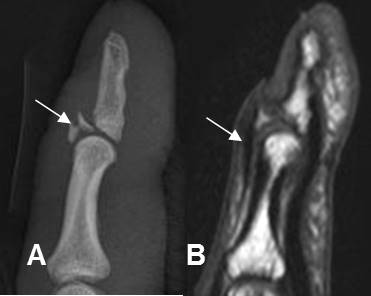

Fig 168. Dedo en martillo.

A: Rx lateral. Avulsión sobre la inserción del tendón extensor, en la base en la falange distal.

B: RM sagital en T1. Se confirma la avulsión. El tendón extensor se aprecia íntegro.